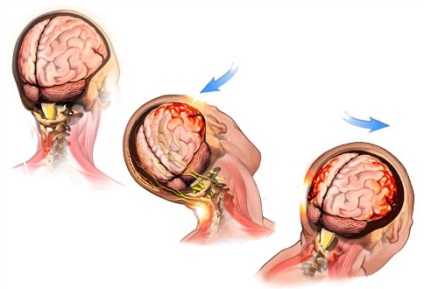

Trauma este efectele primare și secundare.

- Atunci când primar a constatat reacțiile imediate - leziune a pielii și a țesuturilor osoase craniu, distrugerea celulelor creierului. Formată locul leziunii de localizare, în care vasele sanguine ruptură, deteriorarea proceselor nervoase, o vânătaie a trunchiului cerebral. Încasări încălcare a corpului structurii la nivel celular. Ca urmare, procesul de seturi de necroză tisulară inițială, combinată cu formarea de edem.

- Secundar (ischemie) apar din cauza efectelor primare și sunt exprimate ca reacția inflamatorie la prejudiciu. contuzii cerebrale caracterizate printr-un eșec în procesul de hrănire a celulelor cu oxigen, precum și mecanism de schimb de calciu-sodiu. Ei aglomera de calciu, provoacă-le la ruptura si atrofie.